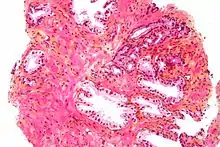

Microscopic glands of the prostate

Microanatomy of a prostatic gland, showing both luminal cells and surrounding basal cells. H&E stain.